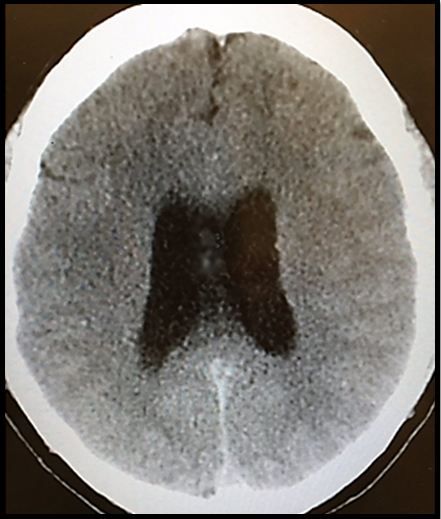

Testing: His head CT scan is shown in Figure 1 at right (Click on image to enlarge)

What does the case image show? Dilated bilateral lateral ventricles from hydrocephalus.

The classic triad for the clinical presentation of hydrocephalus is weird, wet and wobbly, the three Ws. The weird is for dementia, the wet for urinary incontinence, and the wobbly for ataxia. Other symptoms may include headache, vomiting, and changes in vision including diploplia. The physical exam may be notable for nystagmus, cranial nerve 6 palsy, limited upward gaze, and ataxia. Later findings may include loss of vision, which may be permanent, lethargy, brain herniation, and even death.

Initial testing should include a head CT, which is about 70% sensitive overall. In patients who already have a ventriculo-peritoneal (VP) shunt, CT may be falsely negative so the shunt should be tapped to measure the pressure if clinical suspicion for hydrocephalus is high despite a normal head CT. See the highlighted are of the page shot to the right for more information, but be aware that a lot of the information is targeted towards patient who already have a VP shunt.